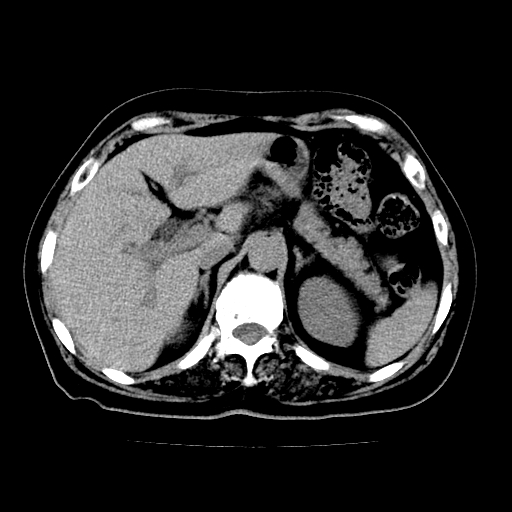

以下是引用zsl6918在2009-2-7 22:12:00的发言:[br]结合临床支持胰腺炎,建议强化查明胆总管扩张的原因。

以下是引用zsl6918在2009-2-7 22:12:00的发言:[br]结合临床考虑胰腺炎可能,建议强化查明胆总管扩张的原因。